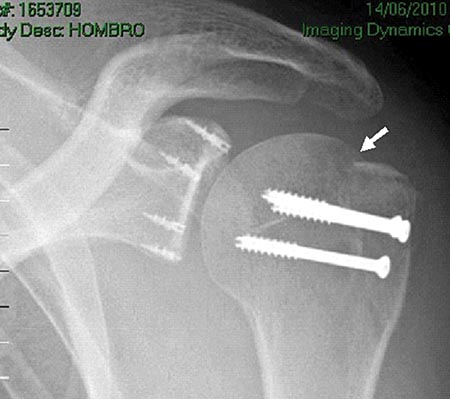

Si la reducción de los fragmentos es correcta en las imágenes por radioscopía, la fijación temporal de los fragmentos óseos con clavijas percutáneas es llevada a cabo. Posteriormente y según el tamaño de los fragmentos se utilizan tornillos canulados de 2.7 mm, 3,5 mm y/o 4.5 mm. Es importante remarcar nuevamente la no resección de los tejidos blandos (manguito rotador) de los fragmentos óseos. En 4casos de fracturas conminutas la reducción y osteosíntesis de los fragmentos fue lograda a través de los tejidos blandos y no del propio tejido óseo. Si la reducción de los fragmentos no es correcta la inspección del lecho de la fractura, primero a nivel articular y luego a nivel subacromial, es llevada a cabo con el fin de facilitar la misma mediante la remoción de tejidos interpuestos. En todos nuestros pacientes fueron colocados no menos de 3 tornillos de fijación (Fig. 1 y 2).

Figura 1C: Espacio subacromial. Reducción artroscópica fractura del troquíter. Se observa línea de fractura./ Figura 1D: Osteosíntesis artroscópica con tornillos canulados de 3.5 mm./ Figura 1E: Reducción y ostesíntesis con 3 tornillos canulados de 3.5 mm. Flecha: pérdida de hueso. Reparación de Bankart y SLAP asociada.